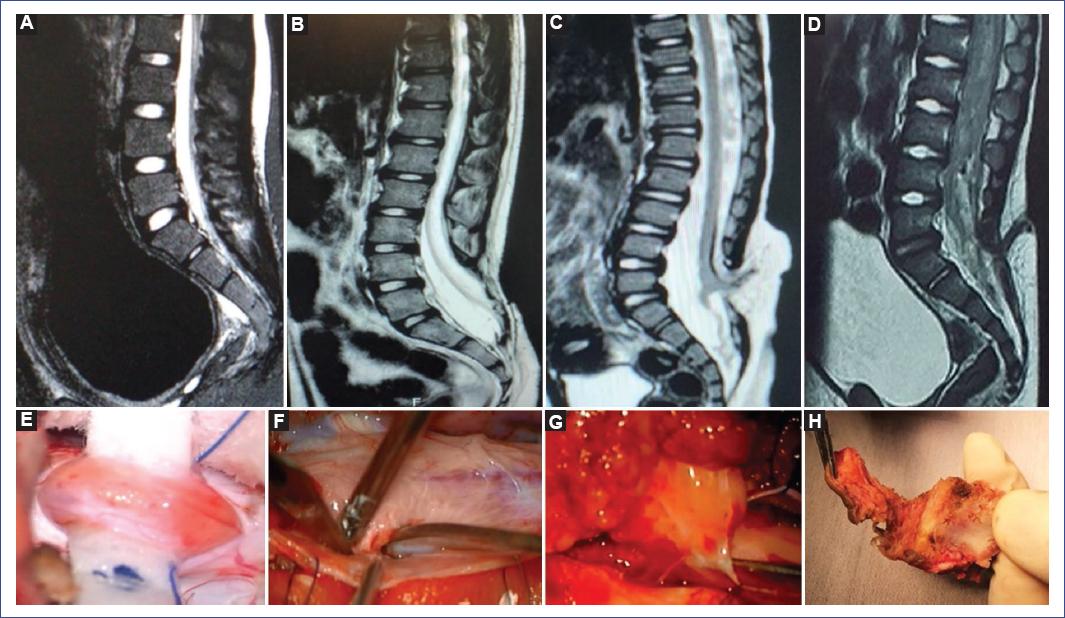

Por grupo etario pediátrico encontramos predominio de afección motora, disfunción vesical y estreñimiento en lactantes, preescolares y escolares; en cambio en los adolescentes y preadolescentes hubo predominio de lumbalgia. Se identificaron estigmas cutáneos en el 61.11% de los pacientes (n = 11), siendo una cola humana, dos hemangiomas en pacientes operados de mielomeningocele, cuatro lipomas subcutáneos y cuatro hoyuelos dérmicos en pacientes con seno dérmico. La figura 1 muestra imágenes representativas de los estigmas cutáneos identificados en nuestra serie. Para el diagnóstico por imagen se utilizó la RM lumbosacra en 17 casos y el US lumbosacro en dos casos, US transquirúrgico en un paciente con cola humana y US como tamizaje diagnóstico en un paciente con hoyuelo dérmico, fiebre y paraplejia, que sugirió un trayecto fistuloso y posteriormente se complementó con RM lumbosacra (Fig. 2). La RM confirmó el diagnóstico de anclaje medular en el 94.4% de los casos. En la figura 3 se ejemplifica la correlación de los hallazgos de anclaje medular por RM y los hallazgos transquirúrgicos en paciente con filum hipertrófico y megavejiga por disfunción vesical (paciente 14), paciente operado de mielomeningocele y adherencia medular a la duramadre (paciente 13), paciente con lipomielomeningocele y lipoma que penetra a la médula espinal (paciente 8) y paciente con seno dérmico, donde se aprecia un trayecto fibroso que atraviesa la vértebra (paciente 7).

Figura 3 Imágenes de resonancia magnética en secuencia T1 en corte sagital en la parte superior y en la parte inferior imágenes intraoperatorias (A y E). Filum lipomatoso y megavejiga en resonancia magnética (B y F). Paciente operado de mielomeningocele con la medula anclada a la duramadre (C y G). Lipomielomeningocele con médula que se ancla al lipoma (D y H). Seno dérmico y trayecto del seno dérmico que atraviesa la vértebra, se evidencia la vejiga incrementada de tamaño en la resonancia magnética.